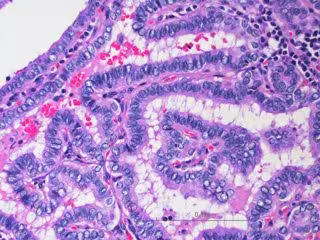

Archivo - Imagen al microscopio de células de cáncer de tiroides, específicamente carcinoma papilar de tiroides, o PTC.

Archivo - Imagen al microscopio de células de cáncer de tiroides, específicamente carcinoma papilar de tiroides, o PTC. - WENDONG YU / BAYLOR COLLEGE OF MEDICINE. - Archivo